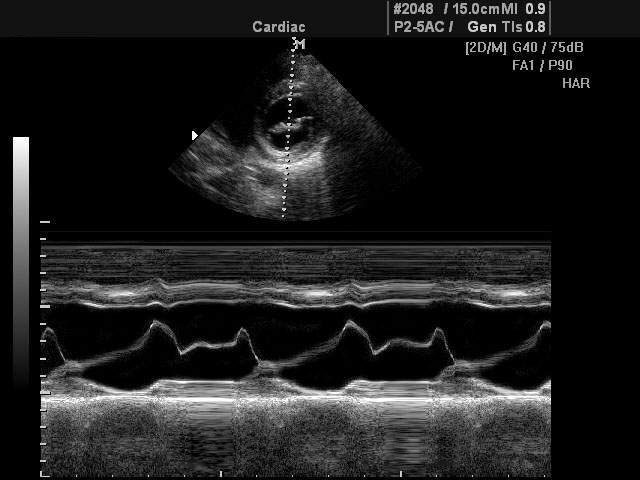

M-режим разработан специально для исследований подвижных структур в реальном времени (от английского motion - движение). Наибольшее применение М-режим нашел в исследовании структур сердца (оценка размеров, сократительной функции сердца, работа клапанного аппарата и т.д.).

При помощи M-эхограммы специалист может количественно оценивать геометрическое смещение подвижных структур и измерять их изменение относительно взаимного положения (просвет в клапанах сердца, изменение размера желудочка и прочее). M-режим зачастую используется вместе с B-режимом (англ. brightness - яркость), во время диагностики врач в B-режиме выбирает необходимый ракурс наблюдения, а затем с помощью курсорной линии на B-эхограмме выбирает направление оси ультразвукового луча для M-режима. Положение датчика фиксируется рукой доктора, после чего включается M-режим.

В М-режиме зондирование периодически повторятся в одном и том же направлении акустического луча. При формировании М-эхограммы в каждом зондировании амплитудная информация об эхо-сигналах с различных глубин отображается в виде отметок различной яркости вдоль вертикальной линии на экране (акустической строки). Следующему зондированию соответствует своя линия, расположенная правее предыдущей, в процессе перемещения столбца с каждым новым зондированием формируется двухмерная М-эхограмма. Положение яркостных отметок по вертикали пропорционально глубине отражающей структуры, например, сердечного клапана.

• Одновременное отображение двухмерной B-эхограммы и M-эхограммы (использование двух режимов одновременно).